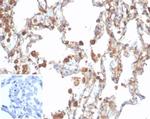

ALDH1A1 (Aldehyde Dehydrogenase 1A1) Antibody in Immunohistochemistry (Paraffin) (IHC (P))

Formalin-fixed, paraffin-embedded human lung stained with ALDH1A1 Recombinant Mouse Monoclonal Antibody (rALDH1A1/7285). HIER: Tris/EDTA, pH9.0, 45 min. 2 °: HRP-polymer, 30 min. DAB, 5 min. {{ $ctrl.currentElement.advancedVerification.fullName }} 验证信息 View more